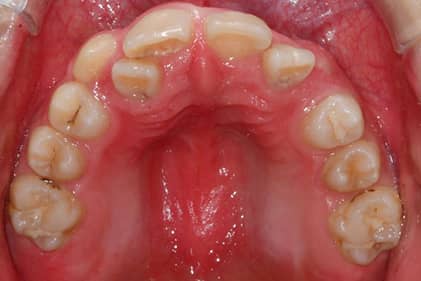

پرونده 1003